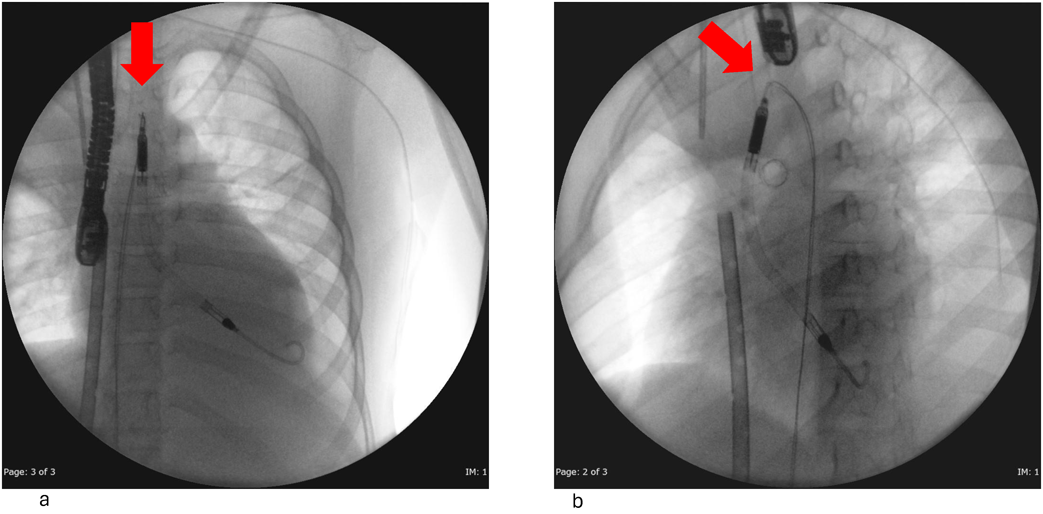

Impella®循環補助用心内留置型ポンプカテーテル(Impella® CP)と静動脈型体外式膜型人工肺により劇症型心筋炎の左室unloadingが著効した12歳男子例—体格の小さい患者における管理上の注意点A 12-year-old male case of successful left ventricular unloading utilizing Impella CP® and veno-arterial extracorporeal membrane oxygenation due to fulminant myocarditis—Precautions for management in patients with small stature